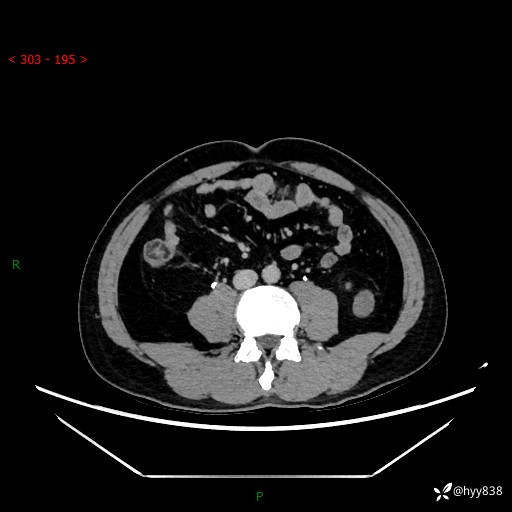

中年男性,左侧腰背部间断性胀痛不适。第一眼“乳头或囊肿”,有无意外---(有结果)

【患者信息】:41岁/男

【主诉】:左侧腰背部间断性胀痛不适1周

【现病史及既往史】:患者1周前无明显诱因出现左侧腰部疼痛,呈间断性胀痛,休息后可缓解,无放射痛,偶可见肉眼血尿,无血块,无尿频尿急尿痛,无夜尿增多,无畏寒发热、咳嗽咳痰等症状。于我院查双肾CT示:左肾占位性病变,左肾下极囊性病变,左肾轻度积水,胆囊多发结石。今为求进一步诊治来我院,门诊以“左肾占位性病变”收治入院。 起病以来,患者精神佳,饮食、睡眠良好,大便正常,小便如上诉,体力体重无明显变化。

【检查】:肾脏CT平扫+增强